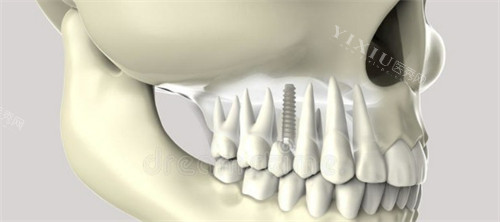

种植牙主要由两部分组成:种植体和牙冠。康盛种植体本身并非全瓷或半瓷材质,其种植体部分采用高强度纯钛金属制成。纯钛因其优异的生物相容性和机械性能,被广泛应用于种植牙领域。这种金属材质能够与人体骨组织形成良好的骨结合,为后续的修复提供稳固基础。

牙冠部分是种植牙可见的修复体,也是患者日常咀嚼和美观的关键部位。康盛种植系统在牙冠修复方面提供了多种选择,主要包括全瓷冠和烤瓷冠两种类型。全瓷冠完全由陶瓷材料制成,不含任何金属成分,具有较好的透光性和自然美观结果。烤瓷冠则是在金属基底上覆盖瓷层,属于半瓷性质的修复体。